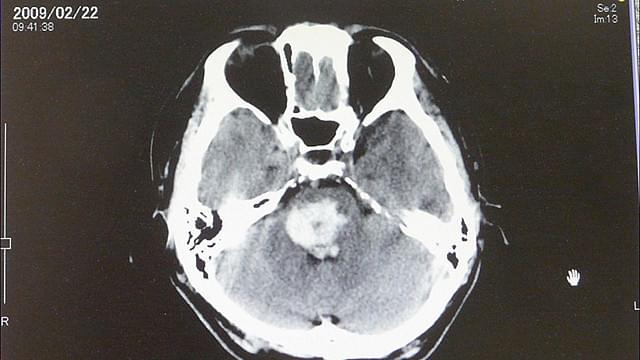

脳幹出血で倒れ、植物状態に陥った特別支援学校国語教諭の宮田俊也さんの入院生活を記録し、絶望的な病状から徐々に回復する宮田さんの姿を通して、生きることの希望を描いていくドキュメンタリー。障害を持つ子どもたちのために奮闘する親友の山元加津子さんに共感し、山元さんをさまざまなかたちでサポートしていた宮田さんは、42歳という若さで突然、脳幹出血で倒れる。一時は命も危ぶまれる状態だったが、現在は意思伝達装置を使って会話をしたり、車椅子に乗って外出もできるほどになった。奇跡的とも言われたその回復の陰にあった、さまざまな人の思いを伝える。監督は、養護学校教諭の山元さんの姿を追ったドキュメンタリー「宇宙(そら)の約束 いのちが紡ぐ愛の詩」も手がけた岩崎靖子。